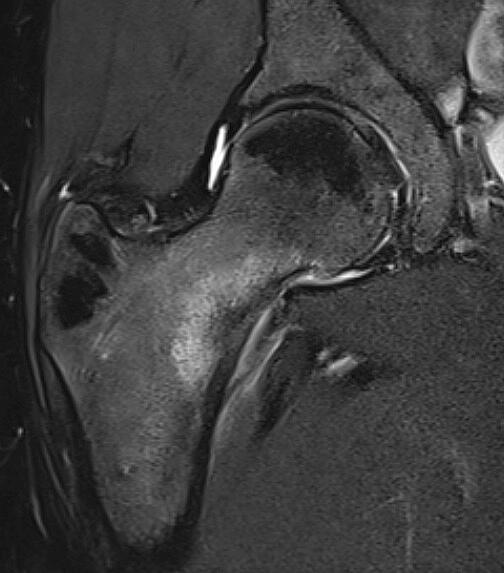

Patellar tendinopathy (MRI scan)

Adolescent osteochondral injury (MRI)